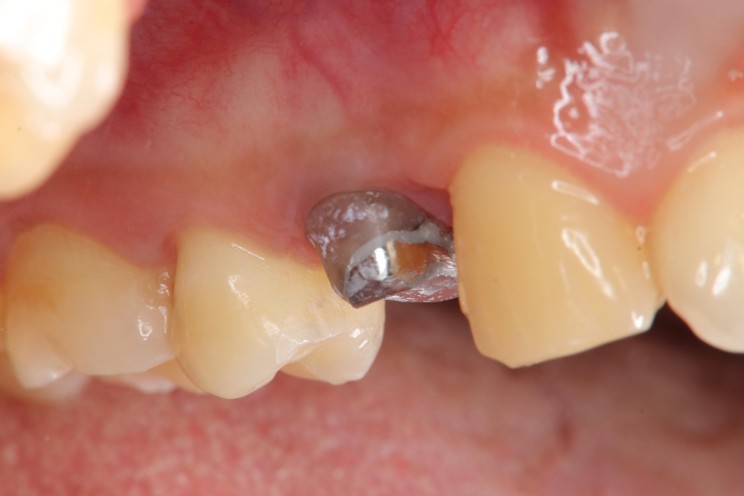

膺復前評估牙齦、牙齒狀態

照相比色